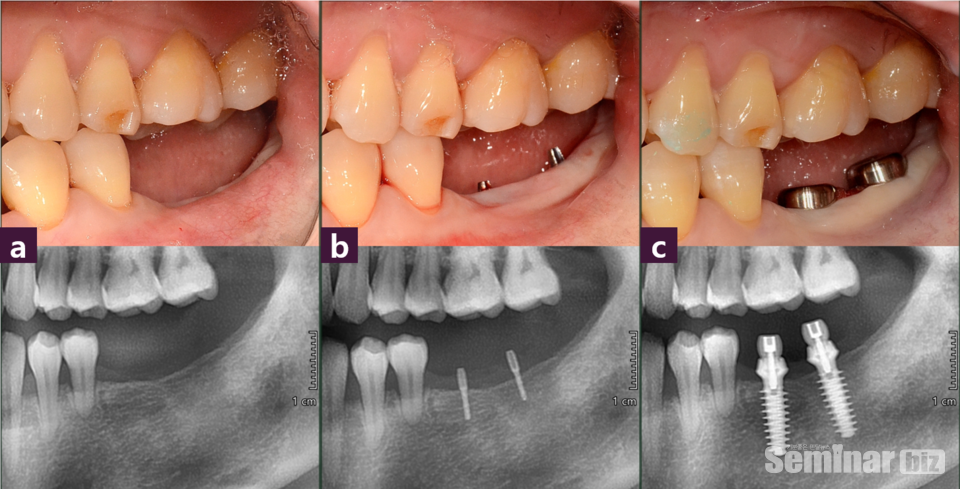

#36, 37 발치 후 2년여의 경과로, CT Axial view에서 #35 협설 치근단면 폭정도로 위축된 #36 치조제를 확인할 수 있다.

하지만, 추가적인 GBR 없이 Magic Fin Thread의 특성을 활용하여 좁은 골폭에서 최대 직경의 MagiCore를 식립할 수 있는 치료를 계획하고 한편, 부족한 부착치은은 최소 절개후 협측으로 확장하였다(그림3, 4).

이처럼 협설골폭이 위축된 경우에도 Magic GPS를 활용하는 식립 계획을 세울 수 있었고, 이를 통해 보다 정교한 임플란트 식립을 할 수 있었다.